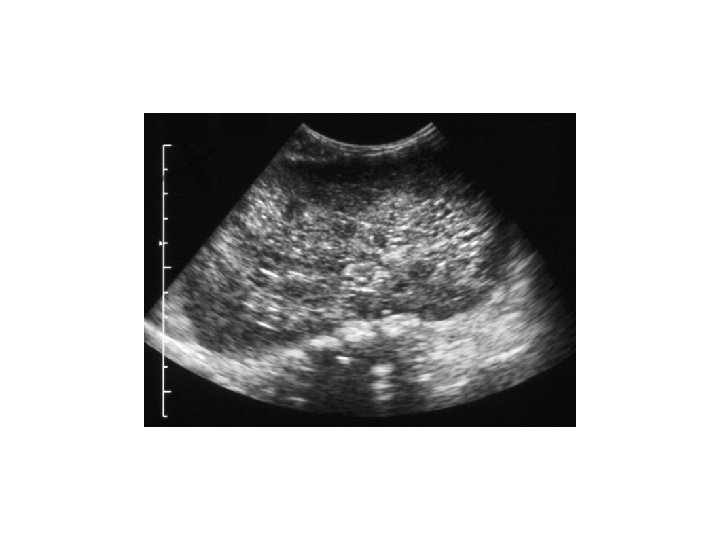

Case 1. . . • • • Generalised oedema by D 2 B/L large abdominal masses Oliguria, low Na, high urea and creatinine Urinalysis blood & protein +++ Abdominal US: B/L PKD, most likely ARPKD, coarse liver.

Diagnosis: • Diagnostic criteria were proposed by Zerres etal: 1. US features typical of ARPKD( enlarged, ecchogenic kidneys with poor CMD and 2. One or more of the following: a) absence of renal cysts in both parents particularly if they are > 30 years old